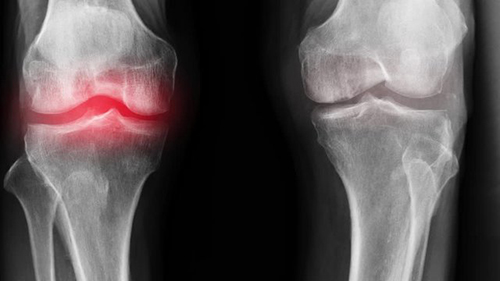

อาการปวดเป็นสัญญาณสำคัญที่บ่งชี้ว่ามีความผิดปกติในข้อ การแค่ทำให้หายปวดจะทำให้สภาพของข้อต่อแย่ลง กระบวนการเสื่อมสภาพจะเร็วขึ้น 3-5 เท่า ส่งผลให้เกิดการเปลี่ยนแปลงที่ย้อนกลับไม่ได้ สูญเสียการเคลื่อนไหวและนำไปสู่การพิการในที่สุด

เมื่อเกลือเหล่านี้เกาะอยู่บนพื้นผิวของข้อต่อ คราบเกลือเหล่านี้เหมือนกระดาษทรายที่ทำลายเนื้อเยื่อรอบโดยรอบ กระดูก และกระดูกอ่อน เมื่อผลึกโตขึ้น เกลือจะเริ่มทำลายเนื้อเยื่อของกล้ามเนื้อ เอ็น หลอดเลือด และเส้นเลือดฝอย ทำให้เกิดการอักเสบ ติดเชื้อ บวม ก่อให้เกิดการอักเสบและปวดอย่างรุนแรง

ในกรณีรุนแรง การสะสมเกลือจำนวนมากอาจทำให้กระดูกหักได้ง่ายเมื่อมีการเคลื่อนไหวอย่างกะทันหัน ส่งผลให้พิการและข้อต่อไม่สามารถเคลื่อนไหวได้